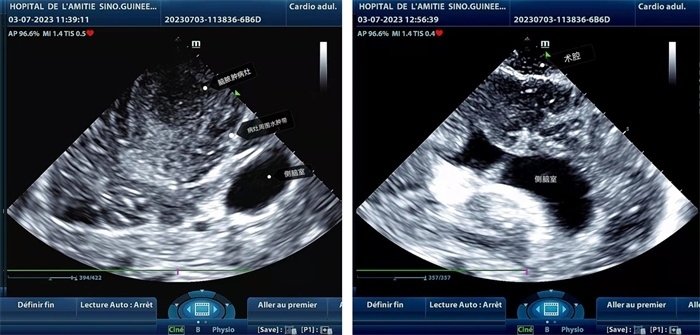

左圖顯示術(shù)中超聲見囊實性病變,大小約為4x4x3cm,病灶周圍腦組織水腫明顯;右圖為病灶切除后,術(shù)中超聲示術(shù)腔無病變殘留

左圖顯示術(shù)中超聲見囊實性病變,大小約為4x4x3cm,病灶周圍腦組織水腫明顯;右圖為病灶切除后,術(shù)中超聲示術(shù)腔無病變殘留。中國第二十九批援幾內(nèi)亞醫(yī)療隊供圖

手術(shù)中,張國濱在超聲科顧秀娟的幫助下,運用顱腦術(shù)中超聲技術(shù),通過將一次性保護套的超聲探頭置于腦組織表面,實時觀察病變的位置和形態(tài),進一步確認最佳手術(shù)路徑。術(shù)中超聲顯示,病變位于左額頂葉,大小約為4x4x3cm,邊界清晰,呈囊實性,周邊腦組織水腫明顯。最終,病灶順利切除,診斷為腦膿腫,并通過超聲檢測確認術(shù)腔無病變殘留、無出血,為患者術(shù)后恢復(fù)提供了良好的保障。